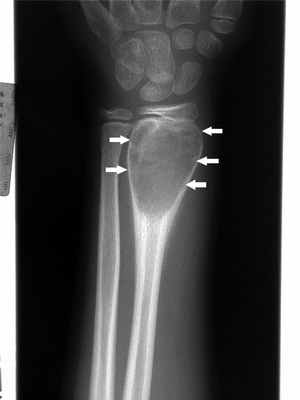

Аневризматическая костная киста – это увеличивающееся идиопатическое образование, возникающие обычно в возрасте до 25 лет. Это кистозное поражение обычно возникает в метафизах длинных трубчатых костей, но и почти все другие кости могут быть затронуты. Она, как правило, растет медленно. Периостальная новая костная оболочка формируется вокруг экспансивного поражения и часто шире, чем исходная кость. Характерны боль и локальная припухлость. Прежде чем будет установлен диагноз, проходит от нескольких недель до года.

Характерна рентгенологическая картина: область просветления обычно четко очерчена и расположена эксцентрично; надкостница выпячивается ("мыльные пузыри"), выдаваясь в окружающие мягкие ткани, а может быть окружена новообразованной костной тканью. МРТ обычно показывает уровень жидкости. При визуализации некоторые аневризматические костные кистовидные поражения могут выглядеть более угрожающе, напоминая по характеристикам остеосаркому, поэтому могут возникнуть подозрения на телеангиэктатическую остеосаркому Остеосаркома (остеогенная саркома) Первичные опухоли костей встречаются значительно реже, чем метастатические опухоли костей, особенно у взрослых. К первичным опухолям костей относятся множественная миелома, остеосаркома, адамантинома. Прочитайте дополнительные сведения , расположенной на самом конце кости.